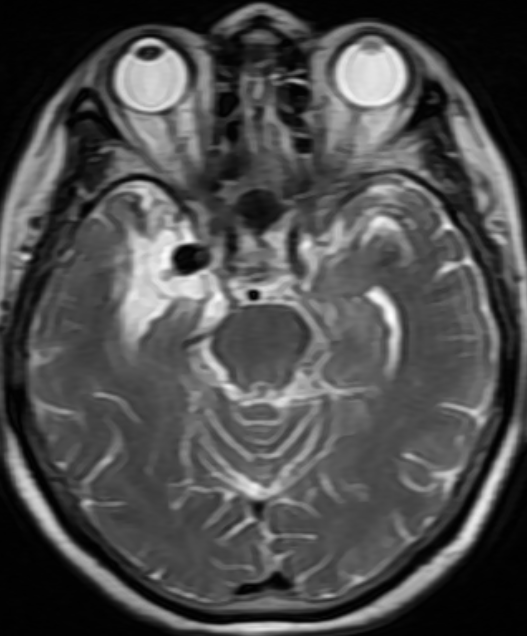

外院头颅MR示:右侧颞叶内侧血管流空影,考虑:颅内动脉瘤

入院后完善头颅CTA:右侧颈内动脉后交通动脉瘤。

后交通动脉瘤大小约22mm*12mm。